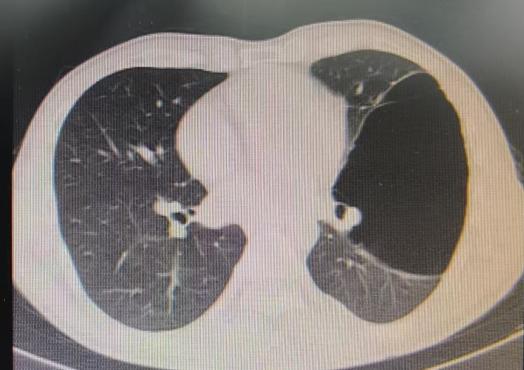

患者信息及手术操作:38岁的李先生(化名)最近总算松了一口气。多年来一直困扰他的左肺巨大肺大疱(76mm×117mm),在我院呼吸与危重症医学科专家团队的精心医治下,通过微创手术得到了显著改善。

近期,国内知名呼吸介入专家陈愉教授联合我院呼吸与危重症医学科团队,为李先生施行“胸腔镜下肺大疱探查术 + 胸腔闭式引流术”。手术中,陈愉教授运用单孔胸腔镜技术,仅在患者胸壁开了一个1cm的小切口。通过高清胸腔镜系统探查发现,患者胸腔内存在广泛粘连以及多发微小肺大疱,肺叶解剖结构异常,肺门血管直接暴露,经判断肺大疱腔已与胸腔贯通。

面对这一复杂状况,陈教授凭借丰富的经验果断调整手术方案。在确保安全的前提下,对可疑病灶进行了精准活检取样,随后精准置入胸腔引流管。术后即刻CT确认引流管位置良好,同时制定了严密的术后管理方案:每日监测引流量及肺复张情况,若引流量持续减少且肺大疱逐渐缩小,则按计划拨管;若肺大疱未明显缩小,则考虑拔除引流管后转外科进行胸膜剥离术。

术后复查CT显示,肺大疱明显缩小,患者胸闷症状显著减轻。整个手术过程进展顺利,患者术后恢复良好。

(术前左肺肺大疱明显-术后肺大疱逐渐缩小闭合)